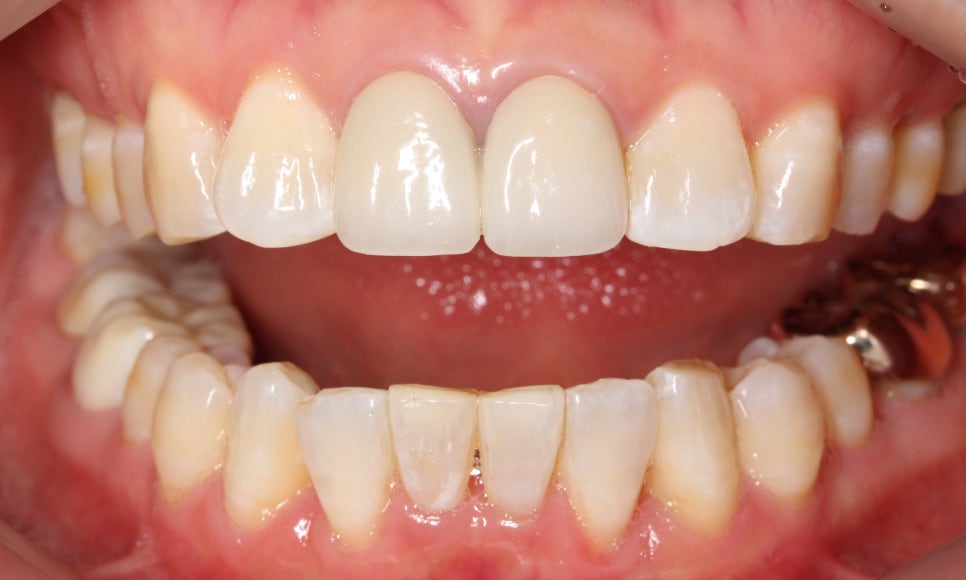

윗니에 가려져서 거의 보이지 않았던

아랫니도 아랫니 부분교정(2D교정)을 통해

정상적인 교합상태로 바뀐 모습입니다~